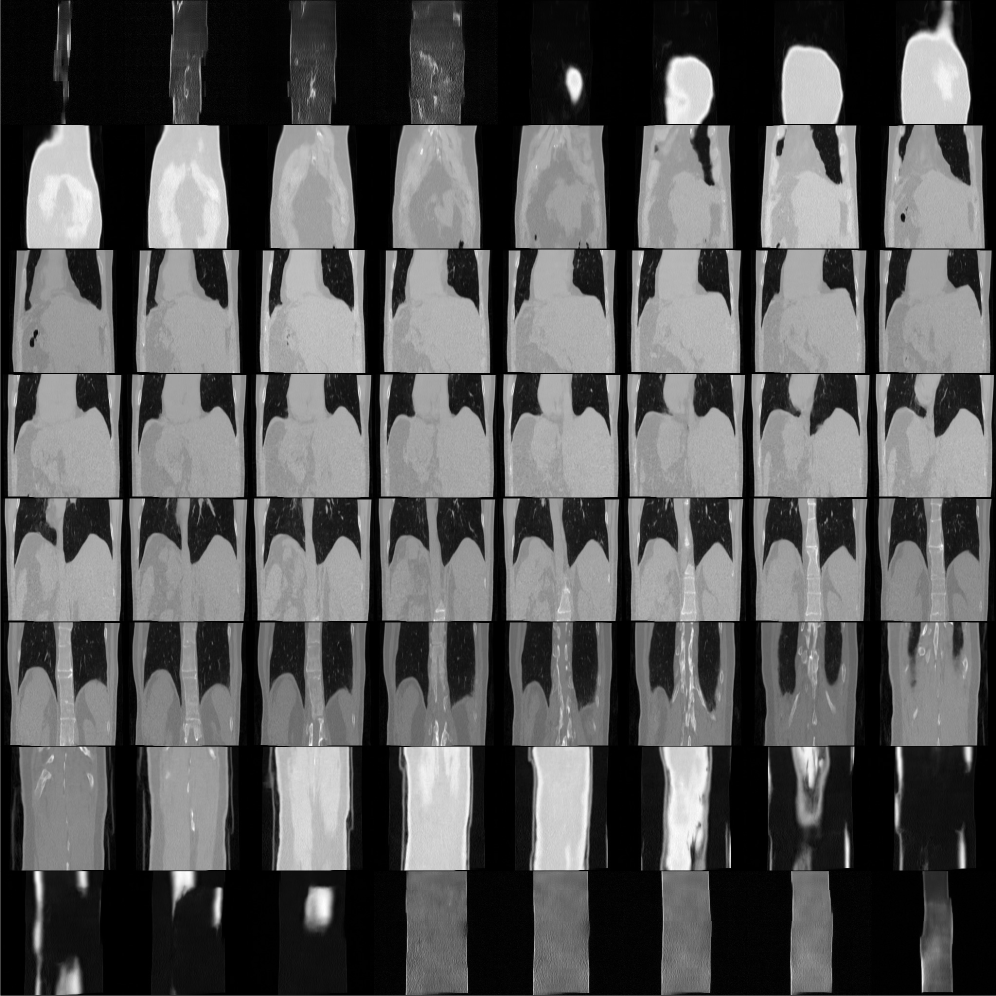

Figures 131415 show unconditional sampling results of 512×512×256512\times 512\times 256, 256×256×256256\times 256\times 256 LIDC-IDRI prior and 256×256×256256\times 256\times 256 AAPM prior. Here, our proposed method is capable of generating realistic volumes, even from the 256×256×256256\times 256\times 256 AAPM dataset that consists of only 9 training volumes.

Refer to caption

Figure 13: Unconditional sampling examples for three different priors (axial slices of 3D volumes).

Figure 14: Unconditional sampling examples for three different priors (coronal slices of 3D volumes).

Figure 15: Unconditional sampling examples for three different priors (sagittal slices of 3D volumes).

Low generation quality on large volume

Although our proposed method achieves SOTA performance on reconstructing 512×512×256512\times 512\times 256 CT volume, it fails to generate fine-grained details as shown in Figures 131415. We speculate that because the number of model parameters remains the same when training priors on 256×256×256256\times 256\times 256 and 512×512×256512\times 512\times 256 sized volumes, it is difficult to achieve comparable generative performance for the larger volume size.